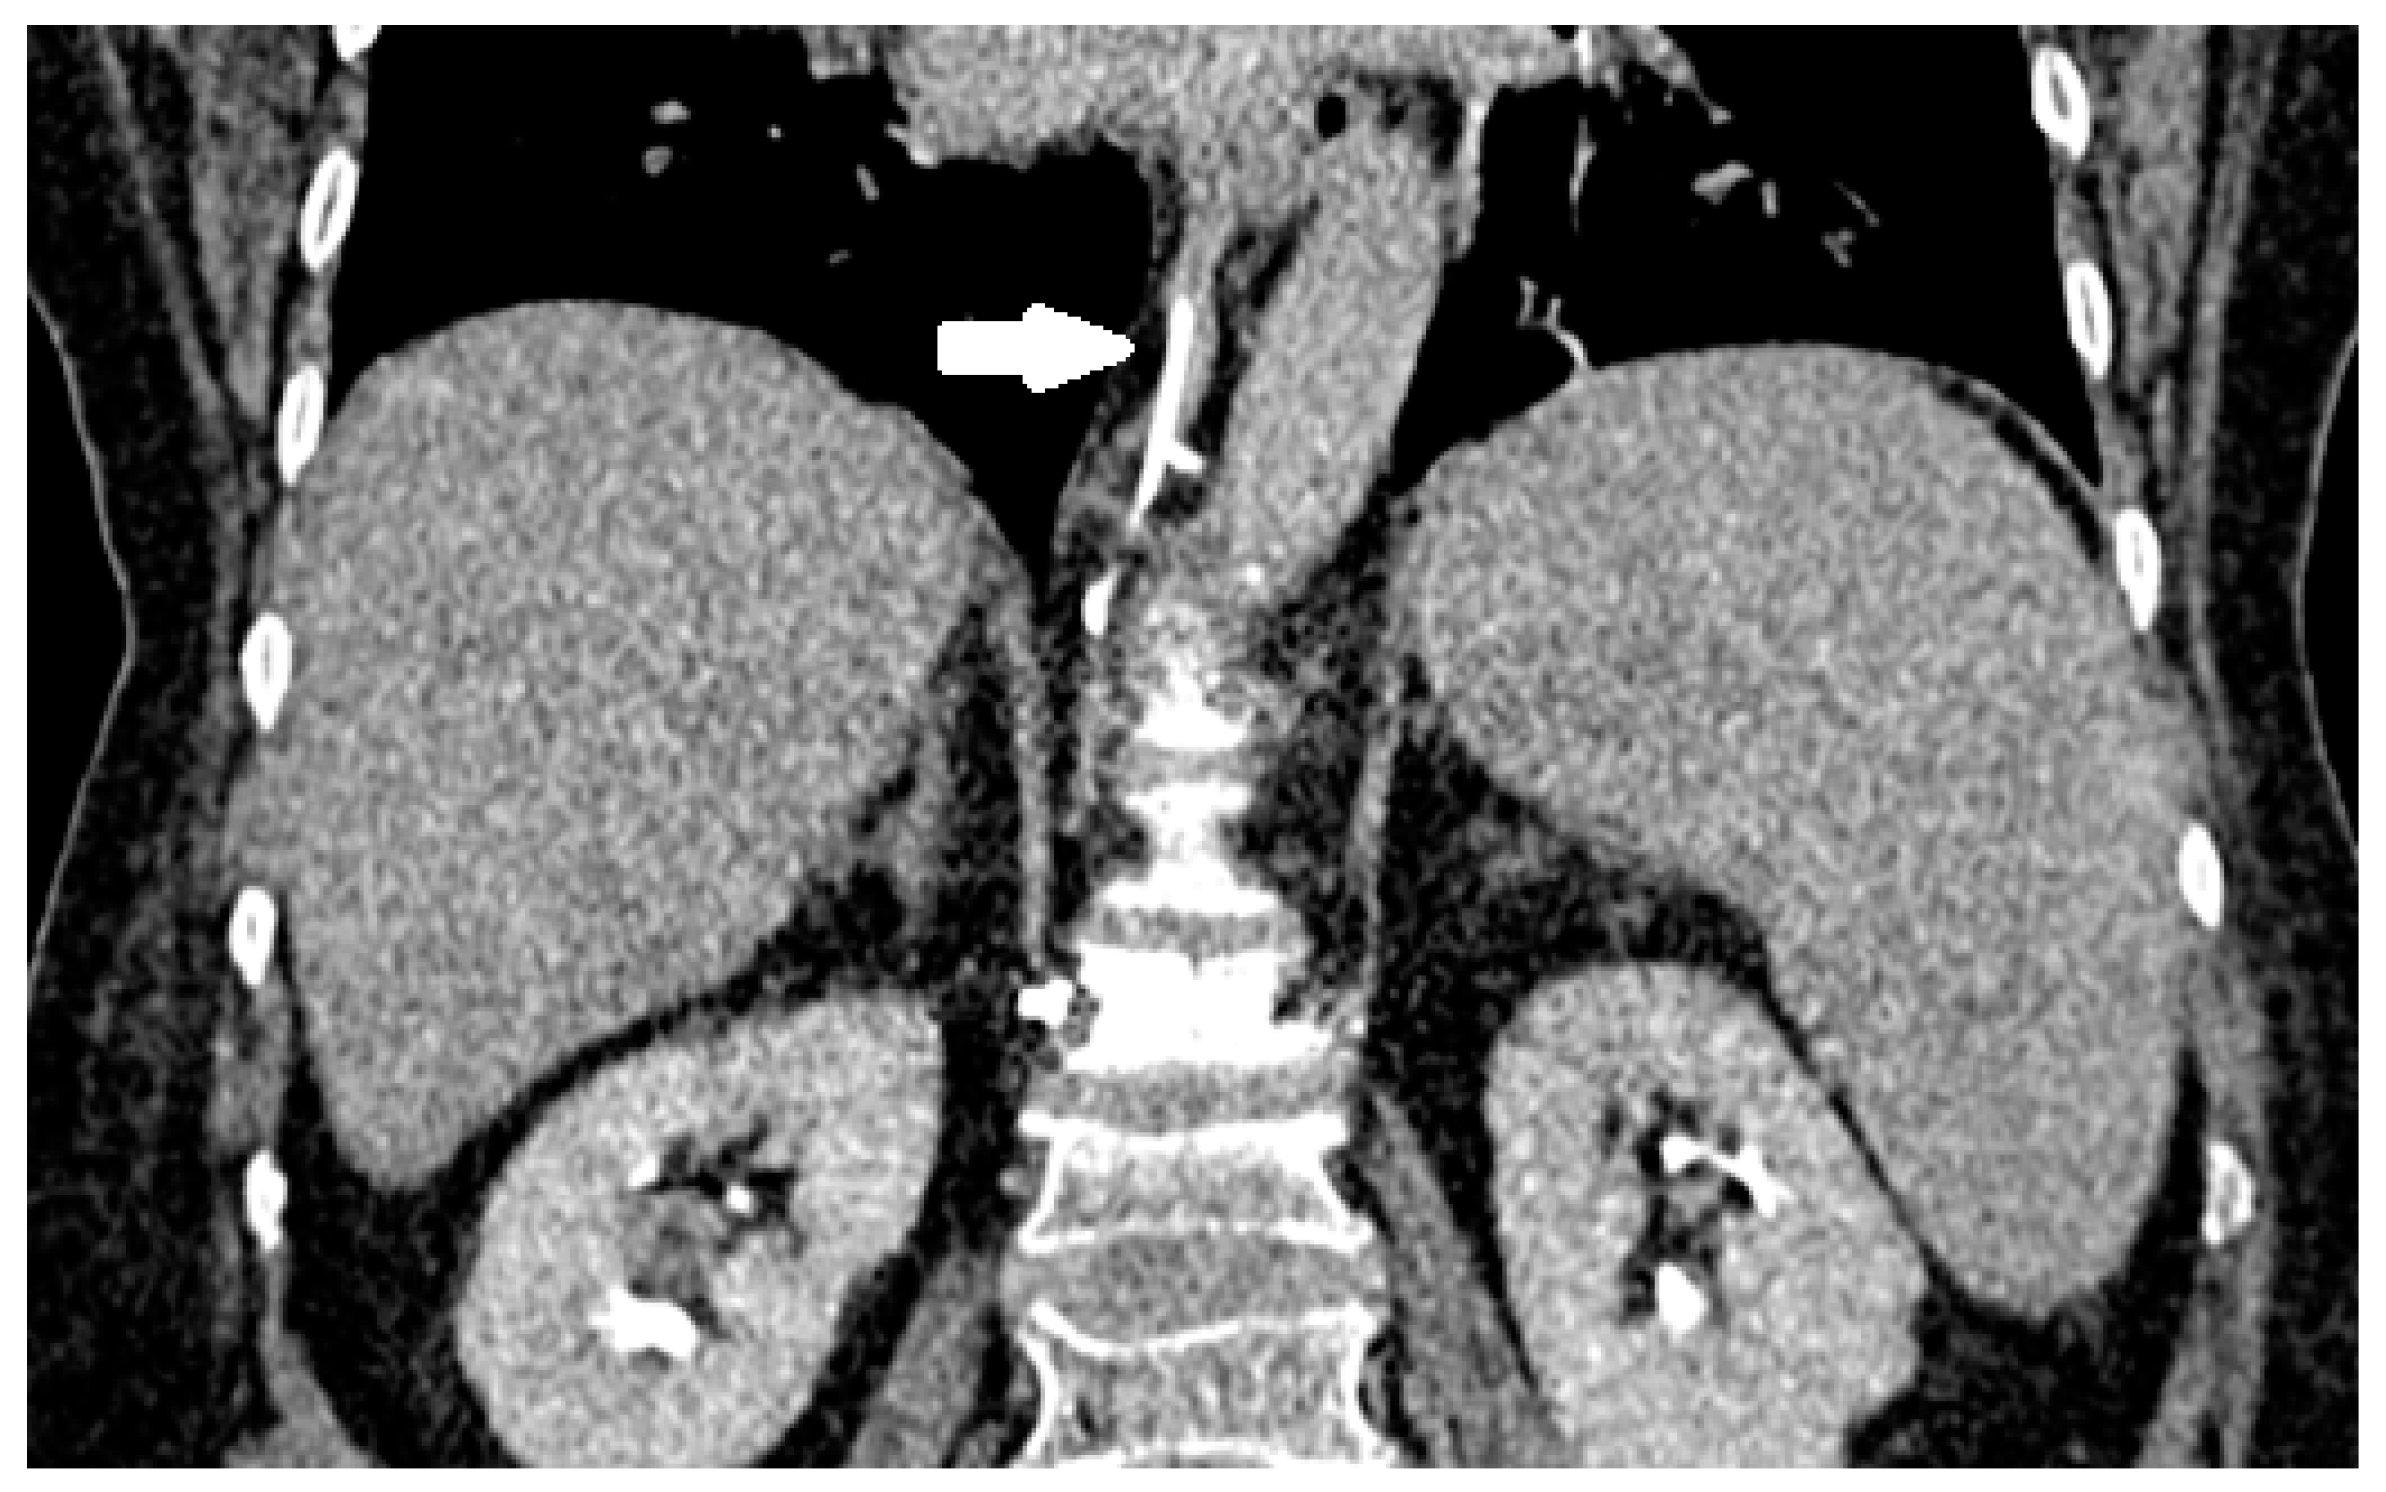

3.4. Venous System Cement Leakage and Pulmonary Embolism